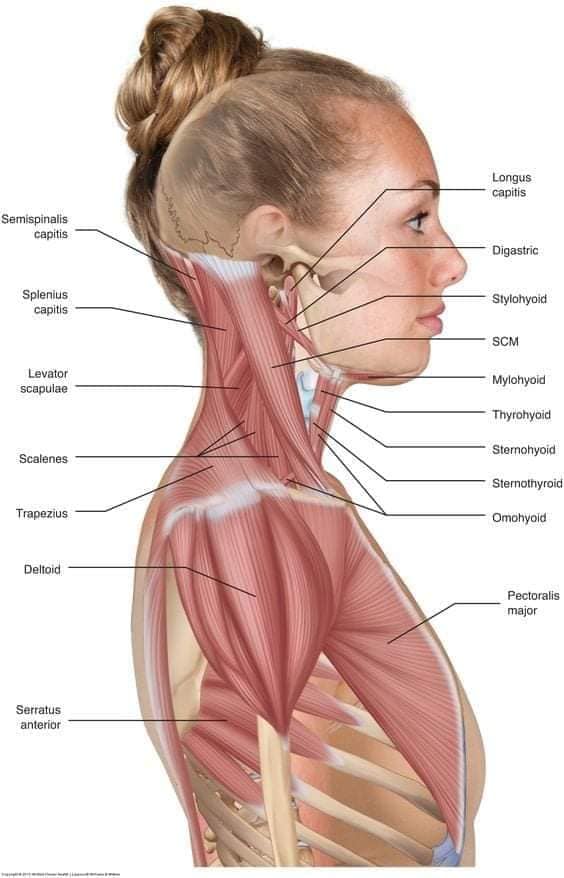

Шийні м'язи

Шийні м'язи мають важливе значення для підтримки голови і забезпечення її рухів.

М'язи передньої групи

М'язи, що згинають шию: М'язи, що згинають голову (м'язи передньої групи): виконують рухи, які дозволяють опускати і піднімати голову.

М'язи бічної групи

М'язи, що повертають голову: Стерноклейдомастоїдний м'яз: один з найважливіших м'язів, який дозволяє здійснювати повороти і нахили голови. Він походить від грудини та ключиці і прикріплюється до соскоподібного відростка скроневої кістки.

М'язи задньої групи

М'язи, що розширюють шию: М'язи, що розширюють шию: включають трапецієподібний м'яз, який бере участь у піднятті плечей і розширенні шиї.